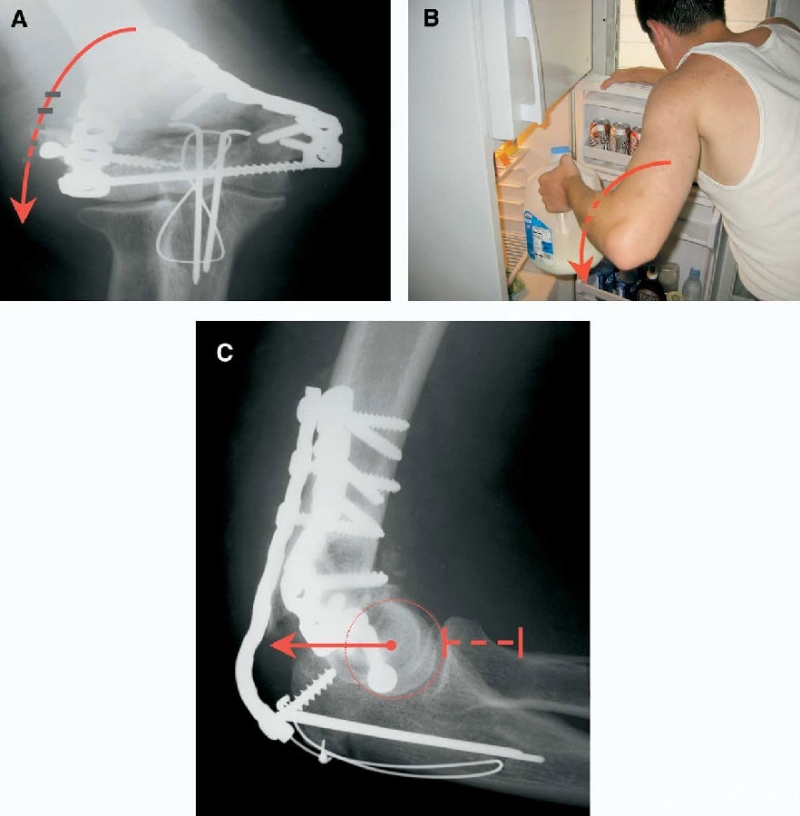

图11 外侧柱失效(内翻)。A:内固定失效通常发生于外侧柱,由于反复的重力和肘关节内翻应力导致。将肘关节正位X线片转至水平位,可以更容易理解施加内翻应力的机制。B:通过将外侧柱钢板放置在侧方的矢状面上,使螺钉在这个方向向内穿过内侧面,可以最大程度减小这种内固定失效机制。C:当肘关节屈曲90°时,内翻应力将外侧柱和肱骨小头从外侧柱后方的钢板上拉开。螺钉失效是由于其被直接从粉碎的骨块中拔出。